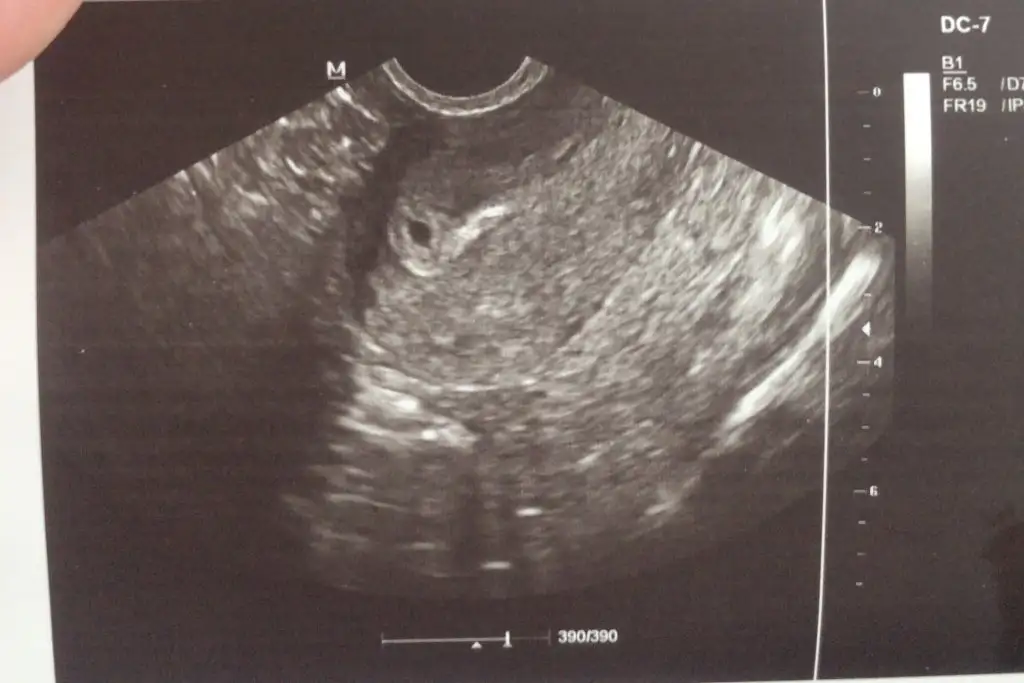

Kızlar ben yine bir vesveseyle geldim tabiri caizse 6+1 de kalp atışını duymuştum bebeğin boyutu crl 2.1 mm daha çok küçük demişti doktor 2 hafta sonra kan tahlili sonuçları için tekrar çağırmıştı.Bugün düşününce boyutu 6+1 e göre normal mi değil mi kafama taktım yine of